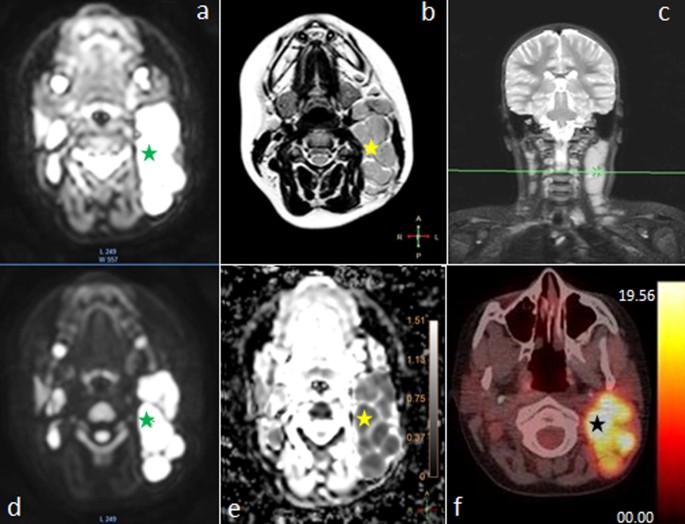

All patients were diagnosed with multiple locations of neoplastic process (median number of 16 locations, range 7–26). Lesions with pathologic features in both imaging methods were termed as recognized regions. The lesion’s SUVmax with each visible 18F-FDG uptake, among all foci was identified. For correlation between apparent diffusion coefficient (ADC) and 18F-FDG quantification, a lesion-by-lesion analysis was performed. In this analysis, SUVmax was recorded for the lesion with the largest diameter and the lowest mean apparent diffusion coefficient (ADCmean) value on the WB MRI (Fig. 1). Due to a better spatial resolution of MRI examination comparing to the 18F-FDG PET/CT, it was possible to delineate nodal groups better and qualify into anatomical regions properly, for instance, not to mediastinal but to axillar or subclavicular region. All regions of increased metabolism visible in 18F-FDG PET/CT presented decreased diffusion in DWIBS. Moreover, values of ADCmean and SUVmax correlated significantly with each other (R2 = − 0.36; p = 0.0002) (Fig. 2).

Fig. 1

figure 1

Images of a 14-year-old girl with Hodgkin lymphoma, showing the same enlarged cervical group of lymph nodes: a WB MRI, axial of b0 DWIBS image hyperintensity restricted diffusion (green star), b WB MRI, axial of T2-weighted image with isointensity region (yellow star); c WB MRI, coronal MIP reconstruction of head and neck STIR image with high signal intensity region (little green cross on green, horizontal line); d WB MRI, axial of b800 DWIBS image subtraction with restricted diffusion region (green star); e WB MRI, axial of ADC map from DWIBS images subtraction with hypointensity restricted diffusion region (yellow star) and ADC scale; f 18F-FDG PET/CT axial image showing 18F-FDG uptake (black star) of cervical region and SUV scale